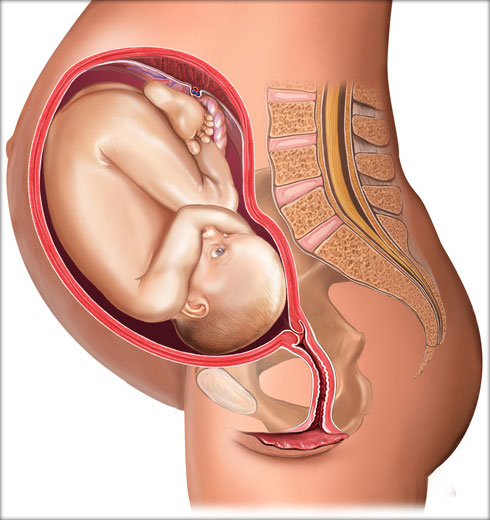

од зачећа 32 недеље